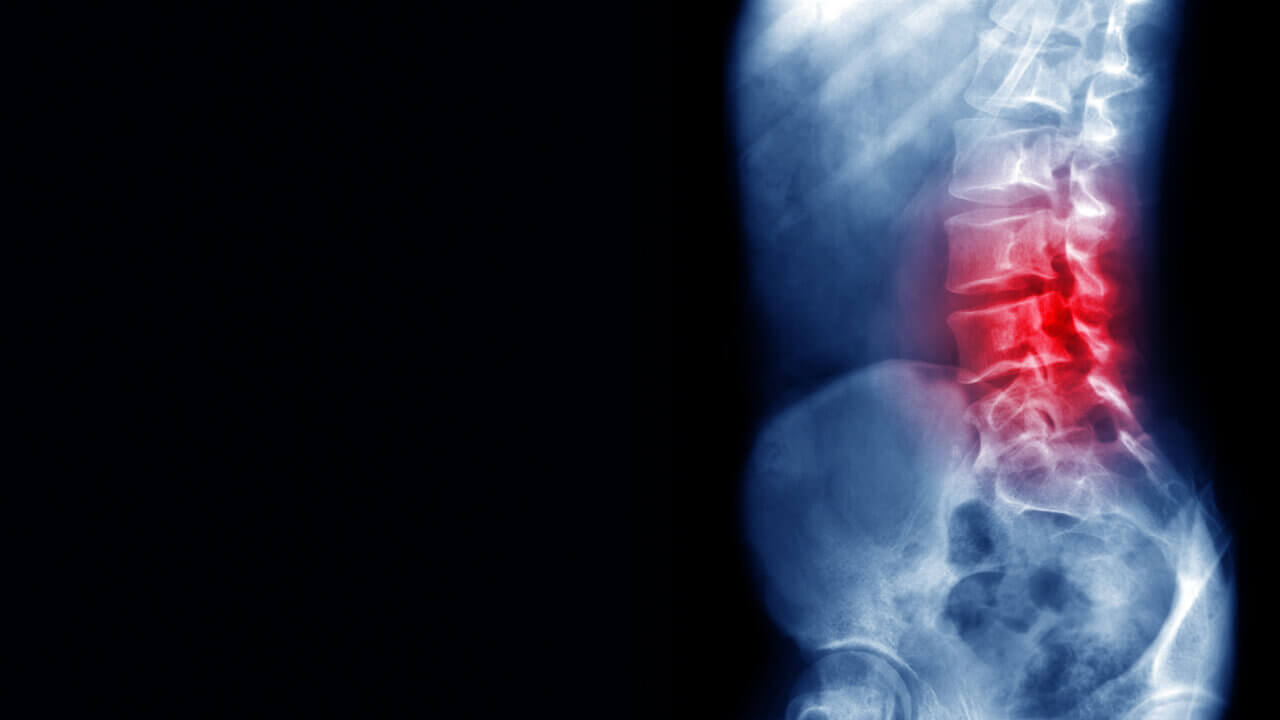

herniated disc causing back pain

A herniated disc is a common condition that occurs when that soft center pushes out through a tear in the covering. It can then press on nearby nerves, causing symptoms. Herniated discs can occur anywhere in the spine but are most common in the lower back.